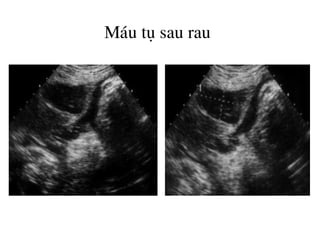

M¸u tô sau rau

Nhåi m¸u b¸nh rau

Tô m¸u trong nhu m« rau